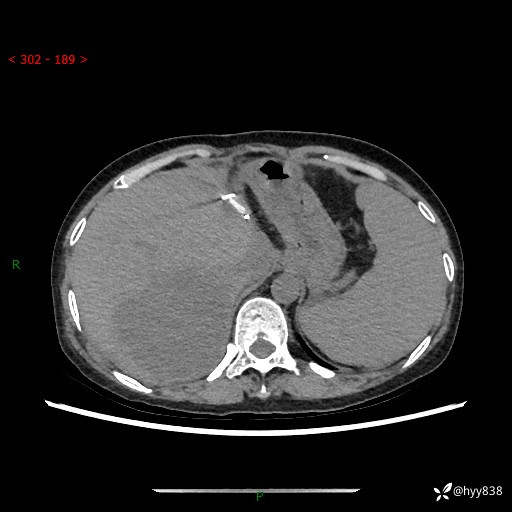

上腹部CT平扫